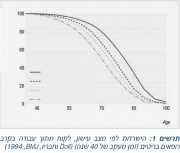

| 15:14, 10 במרץ 2016 | Smoking cessation3.jpg (קובץ) |  |

226 קילו־בייטים | Motyk | 1 | |

| 14:55, 10 במרץ 2016 | Smoking cessation2.jpg (קובץ) |  |

72 קילו־בייטים | Motyk | 1 | |

| 13:54, 10 במרץ 2016 | Smoking cessation1.jpg (קובץ) |  |

111 קילו־בייטים | Motyk | 1 | |